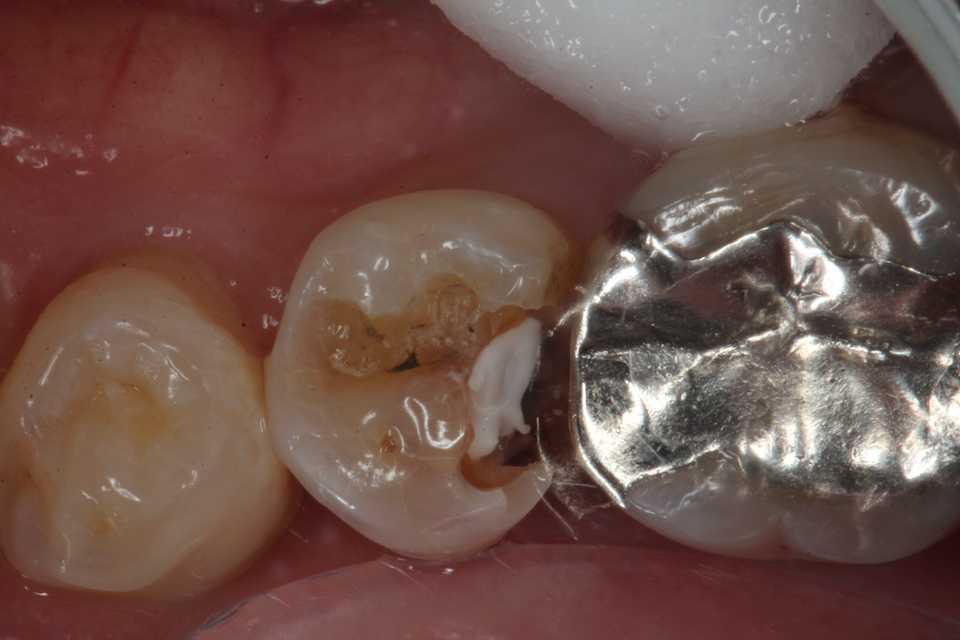

50代女性、右下5、インレー2次カリエス

では時系列でどうぞ